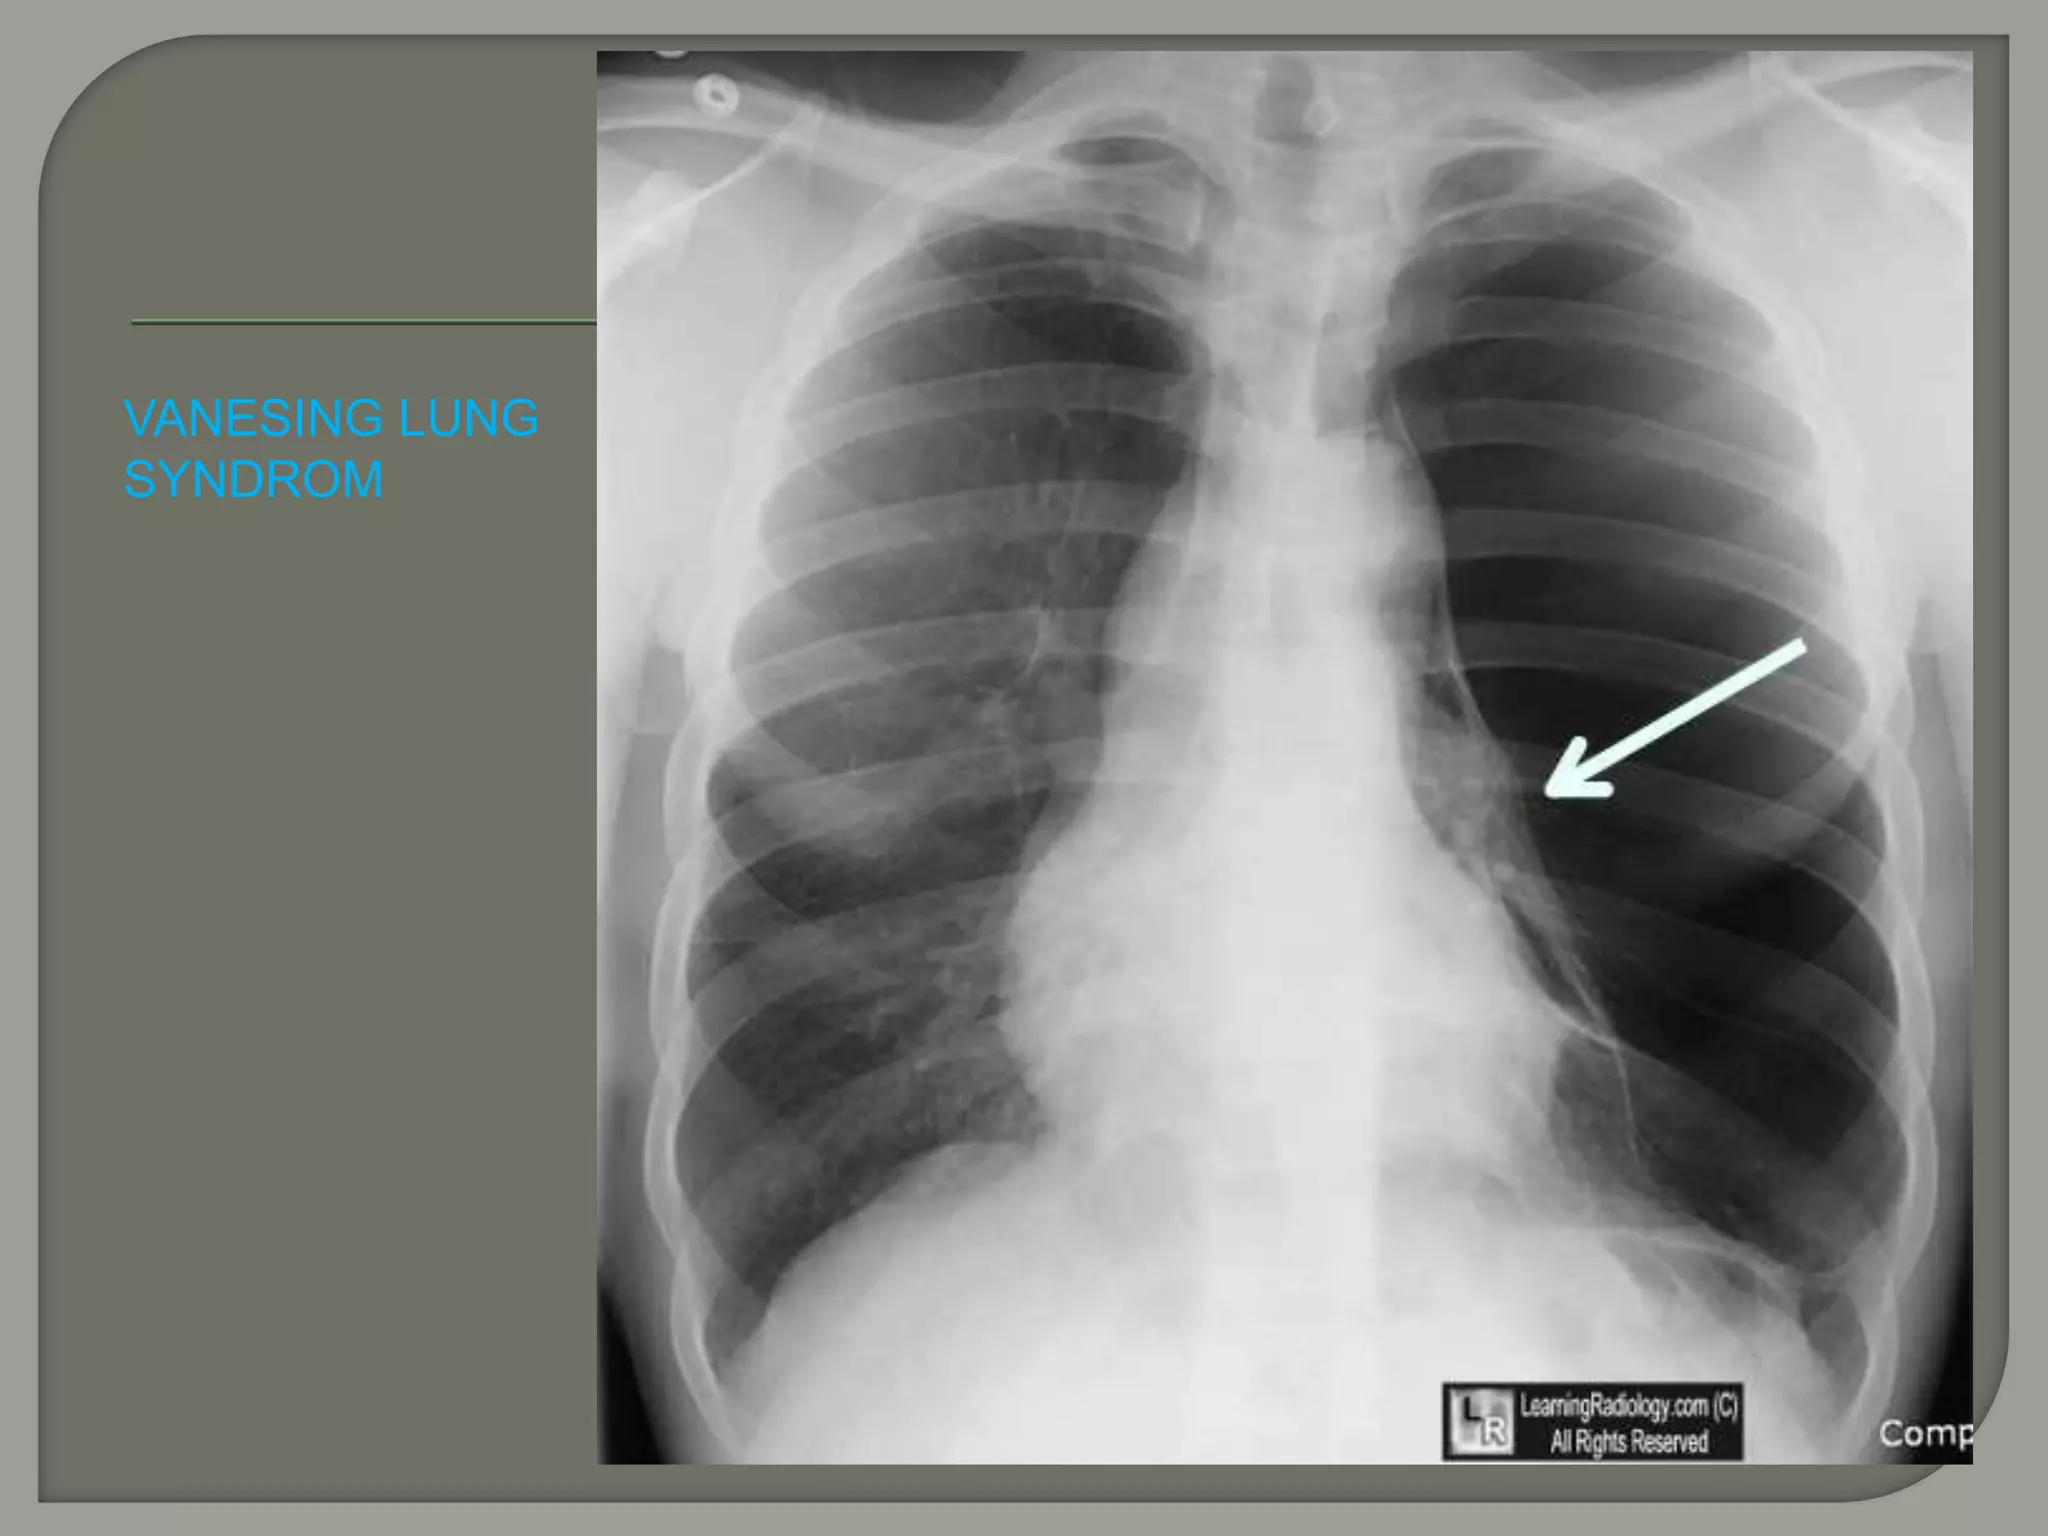

VANESING LUNG

SYNDROM

VANESING LUNG SYNDROM Pneumothorax